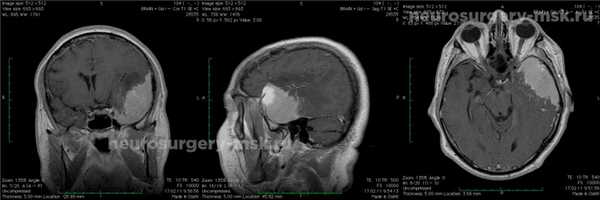

Менингиома средней черепной ямки (до операции)

Лечение: на основании произведенных исследований назначено оперативное вмешательство.